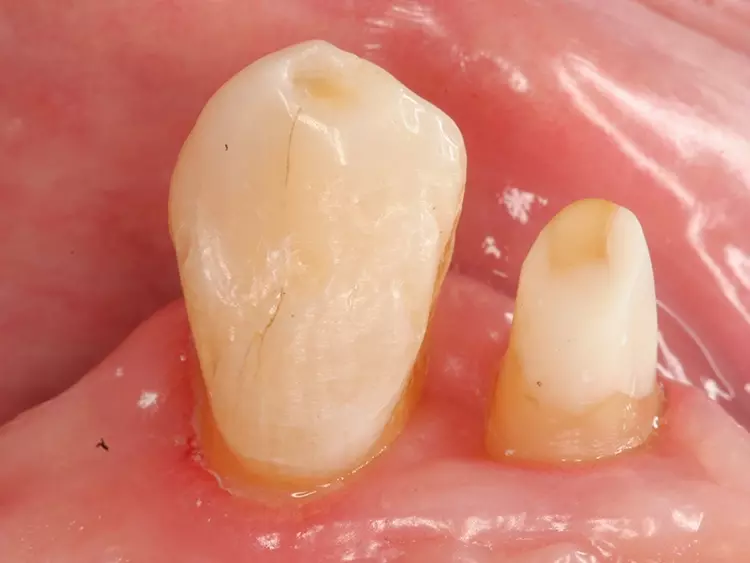

Insbesondere bei konventionellen Geschieben mit Freiendsituationen zeigen sich aufgrund der vergleichsweise invasiven Pfeilerzahnpräparation und der hohen Belastung durch die Prothesensättel häufig Pfeilerzahnfrakturen [2,5,6]. Eine solche, vergleichsweise invasive Präparation birgt zusätzlich die Gefahr der Pulpaschädigung und kann v.a. bei jungen Patientinnen und Patienten mit großen Pulpakammern zum Verlust der Vitalität der Pfeilerzähne führen [7]. Peters verglich den Zahnhartsubstanzabtrag bei Adhäsivpräparationen und konventionellen Kronenpräparationen; er zeigte einen Abtrag von 40% der Zahnhartsubstanz bei konventionellen Kronenpräparationen und 10% bei Adhäsivpräparationen auf [8].

Edelhoff und Sorensen stellten bei konventionellen Kronenpräparationen einen Abtrag von 63 bis 72% der koronalen Zahnhartsubstanz fest [9]. Bei richtiger Indikationsstellung und ausreichendem Schmelzangebot der Pfeilerzähne für eine suffiziente adhäsive Befestigung stellen Adhäsivattachments eine erfolgreiche Therapieoption mit guten Langzeitdaten dar [10-12]. Um eine langfristig stabile adhäsive Befestigung zu gewährleisten, sollten restaurations- und kariesfreie Pfeilerzähne gewählt werden.